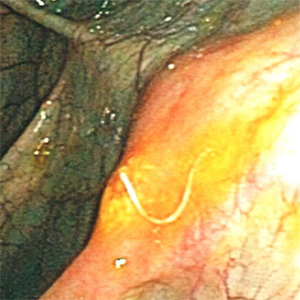

A 23-year-old female with no documented travel history presented with iron deficiency anemia and periodic abdominal pain. Ova-and-parasite (O&P) examinations of stool were negative. A colonoscopy was performed and a worm-like object (Figures A and B) was observed attached to the mucosa of the ascending colon. The object was removed, sent to Pathology, and processed by routine histologic work-up. Figures C–E show what was observed by the pathologist after sectioning and staining with hematoxylin-and-eosin (H&E). Images were captures and sent to the CDC-DPDx for diagnostic assistance. What is your diagnosis? Based on what criteria?

Figure A